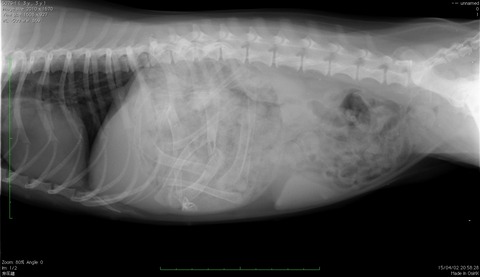

「手羽先を10本くらい・その他いろいろ食べた」との事。 まだ食べた直後だったのでレントゲンで胃の中にあるか確認します。こんなレントゲン写真が撮れました。

○で囲った胃の中に手羽先の骨と思われる白い骨がたくさんあります。 さっそく吐気を催す注射を使って吐かせますが出たのはおよそ6割くらい。 翌日まだ胃の中にあったので内視鏡を使って摘出します。